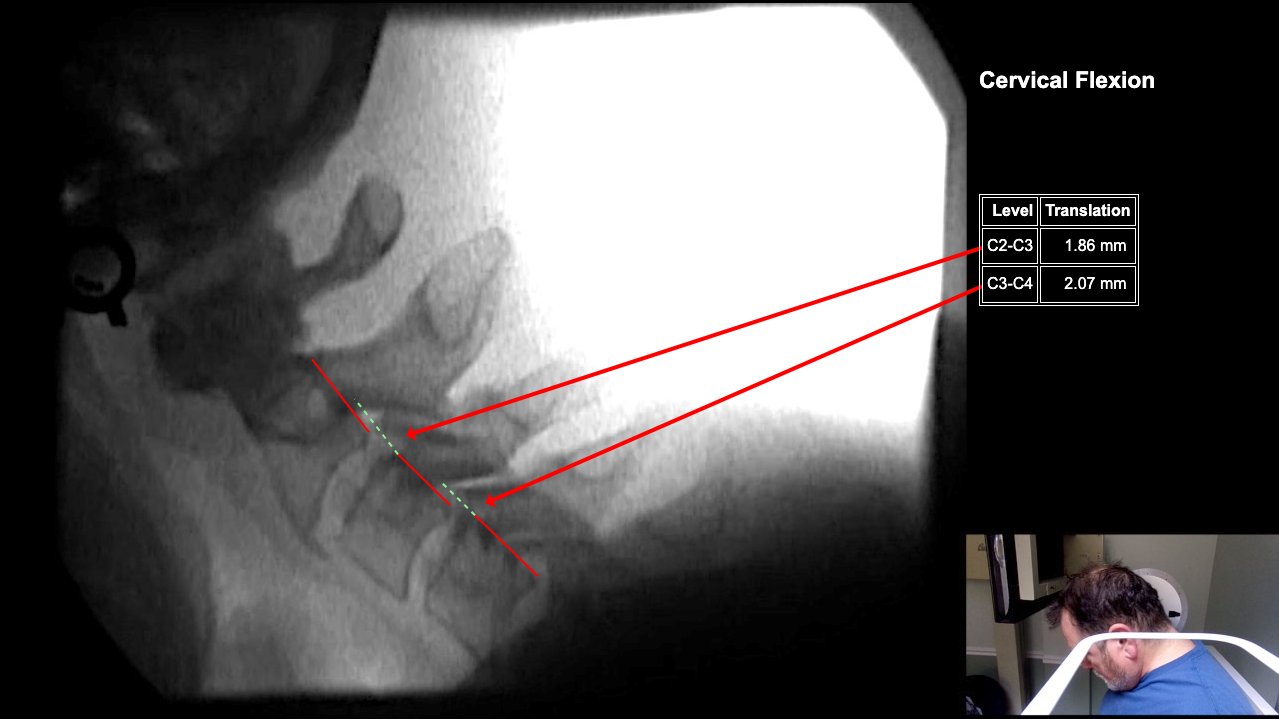

Image 2